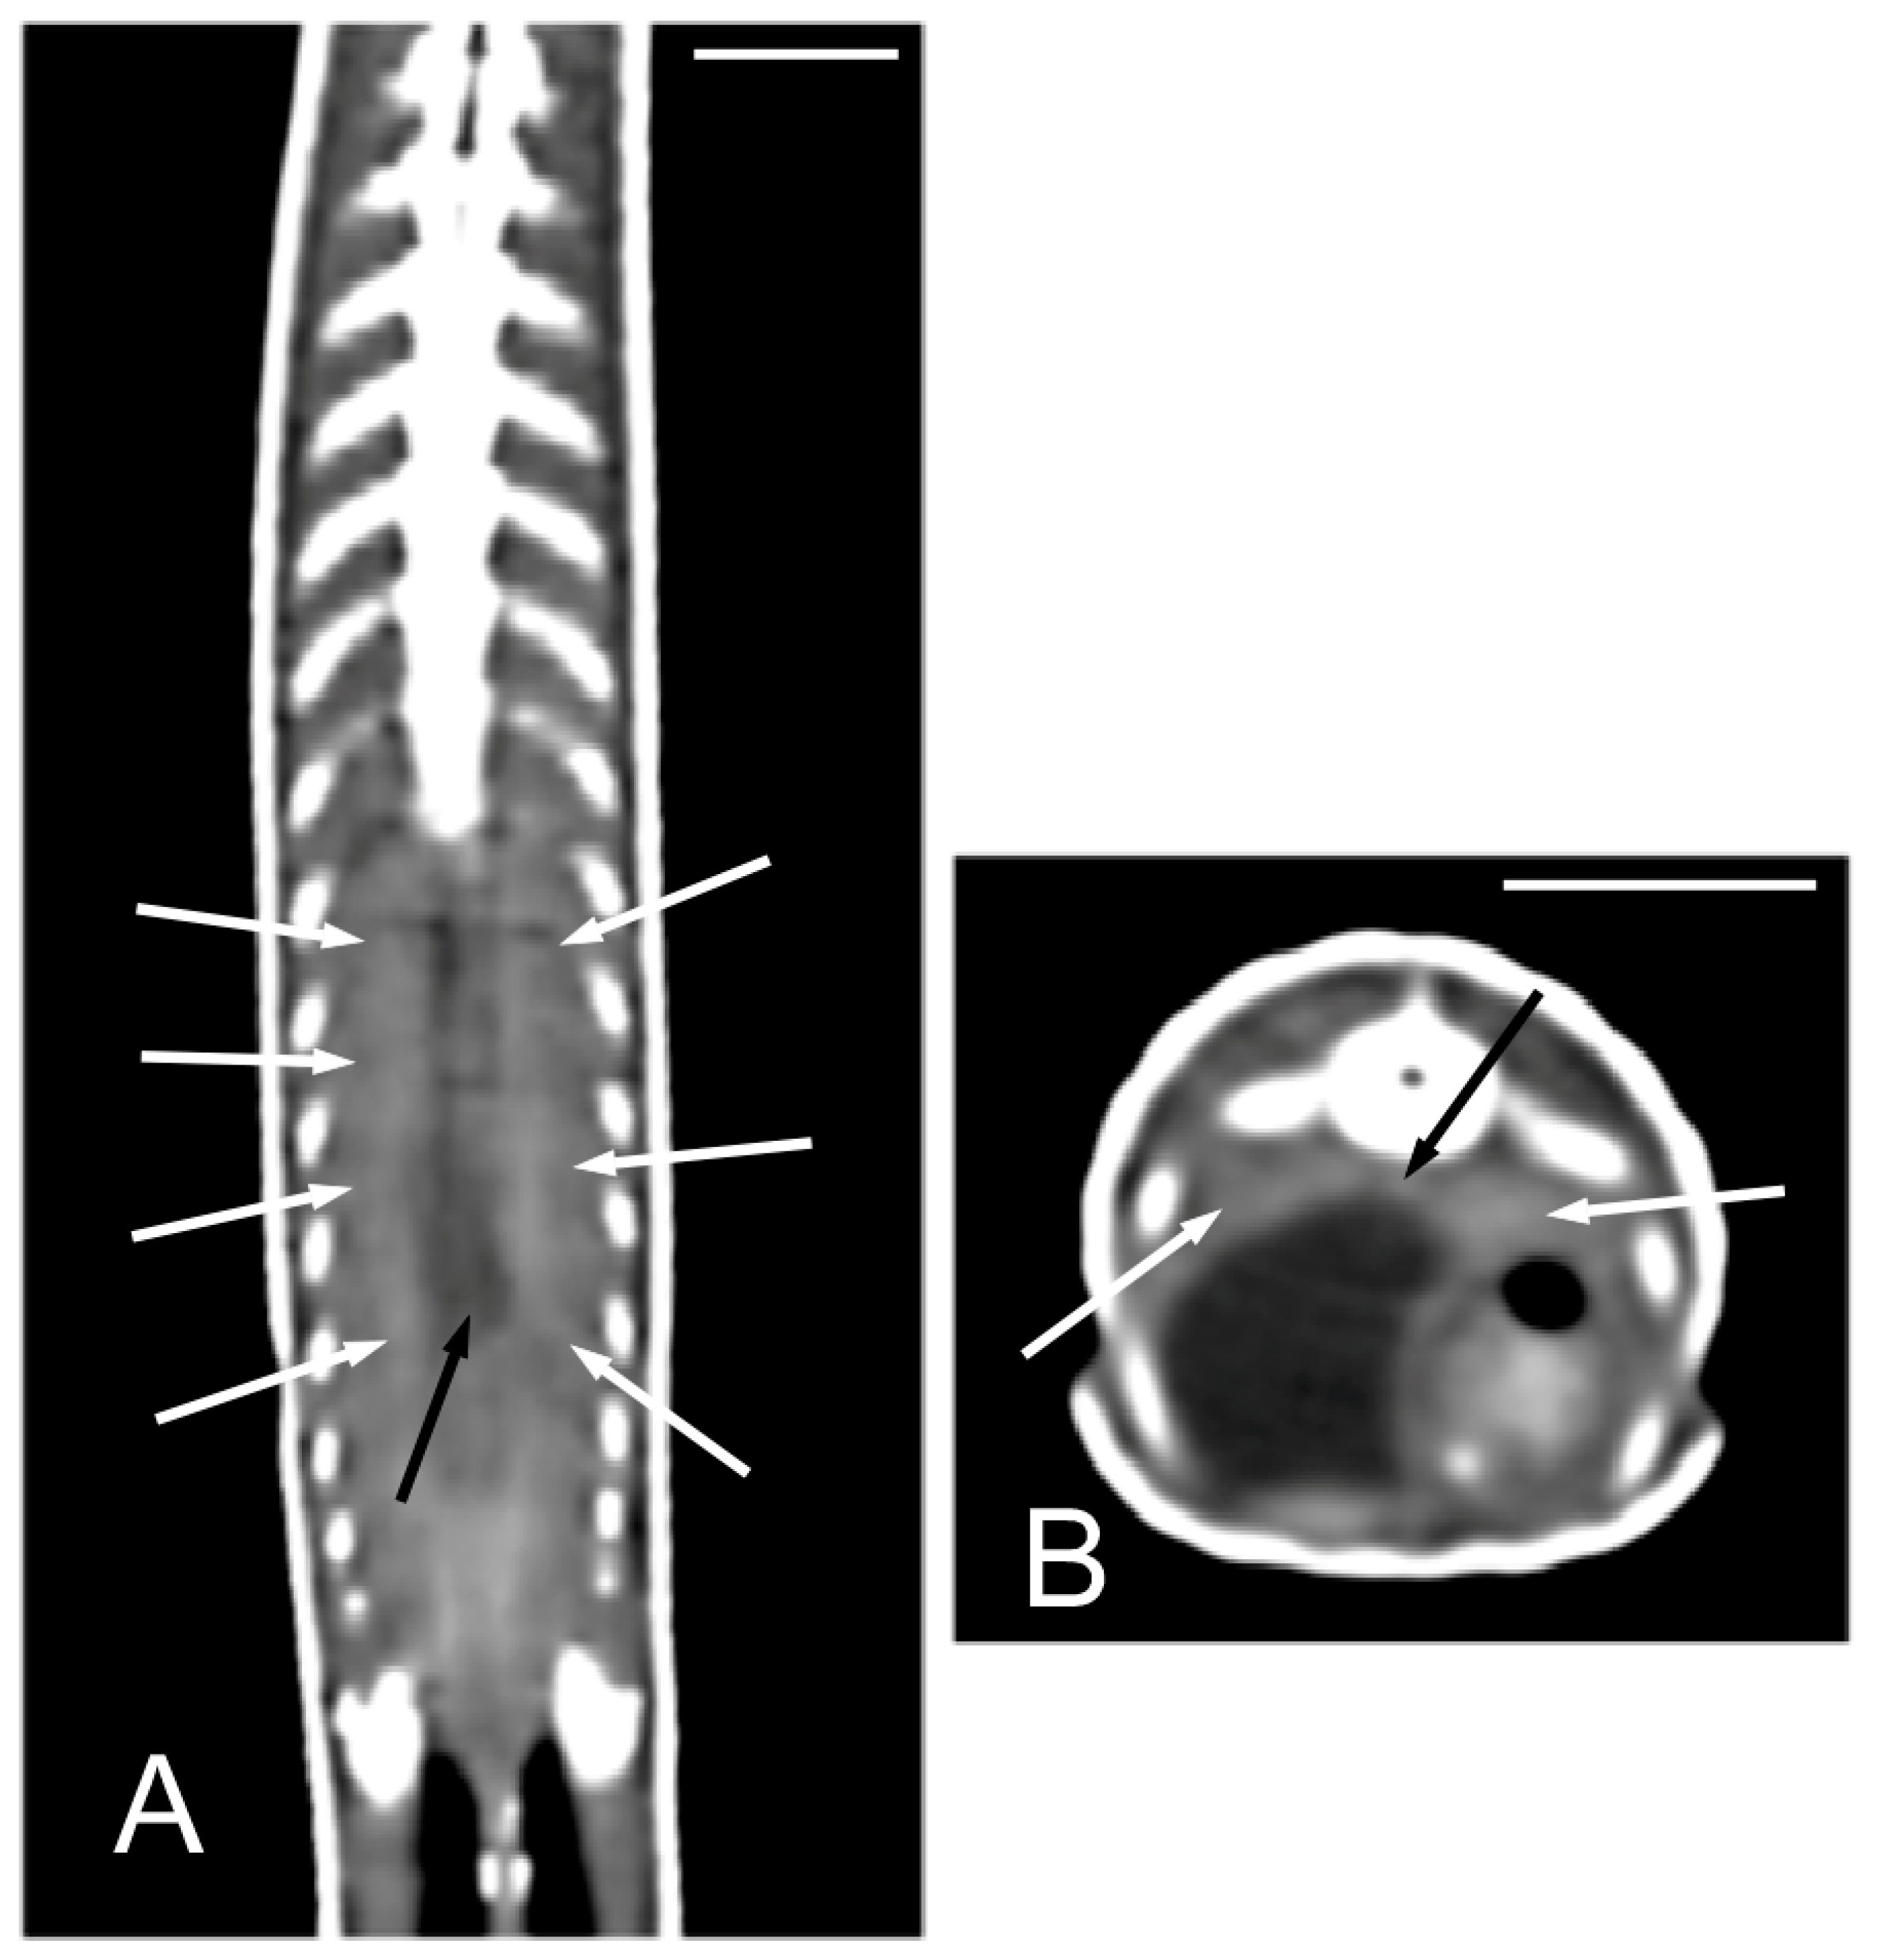

The 3D volume rendering CT images provide a detailed view of the surface anatomy of these individuals (Figure 2A). The lateral groove was readily identifiable in the 3D images (Figure 2B) as well as in the 2D transverse plane images (Figure 2C), in which it was even more evident. The hyperattenuating appearance of the osteoderms layer suggests a high content of bone in them (Figure 2C). The mouth, the nostrils, the eyes, the eyelids, and the otic clefts were easily identified in the lateral view of the 3D volume rendering images (Figure 2B,D) while the parietal eye was also observed in the dorsal view (Figure 2E).

Figure 2.

The 3D volume rendering (A,E in the dorsal view, B,D in the lateral view) and transverse 2D (C) CT images of a specimen of Pseudopus apodus. The lateral groove, mouth, nostrils, eyes, eyelids, otic clefts, and parietal eye are identified. See the list for abbreviations. Bar = 10 mm.

The opening of the vomeronasal organ together with the choanae was identified in the dorsal plane as a V-shaped structure delimited by thin hyperattenuating margins (Figure 4A). The teeth were more distinctly evaluated in the dorsal plane (Figure 4B). The tongue appeared as a hypoattenuating structure located in the ventral part of oral cavity and was more clearly visible in the sagittal plane (Figure 4D). The glottis (Figure 4C–E) was identified as a thin, soft tissue structure with a central opening between the oral and pharyngeal cavities. Although it was visible in the transverse, sagittal, and dorsal planes, it was easier to identify in the latter two.

Figure 4.

The CT images of Pseudopus apodus in the dorsal (A,B,E), transverse (C) and sagittal (D) planes showing the opening of the vomeronasal organ and the choanae (A), teeth (B), tongue (D) and glottis (C–E). See the list for abbreviations. Bar = 10 mm.